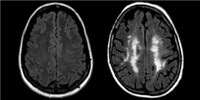

Enticott has also seen differences between children with high-functioning autism and those with Asperger’s in a study that used transcranial magnetic stimulation. The children with autism in that study showed reduced motor cortical inhibition, which typical kids and those with Asperger’s did not (Developmental Medicine & Child Neurology, 52:e179-83, 2010). Those findings suggested an explanation for the motor problems seen in autistic kids.